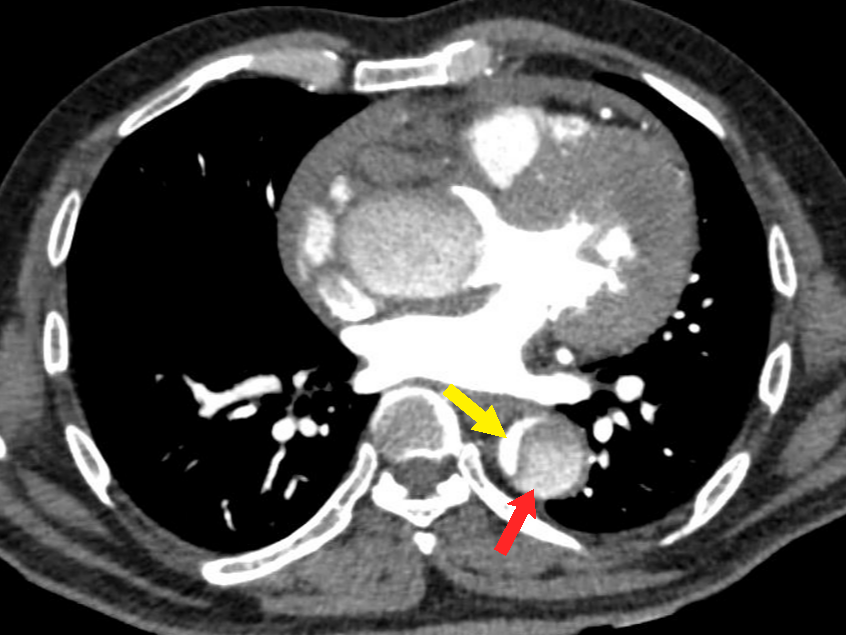

Figure 4 Axial CT angiography image in the arterial phase shows an aortic dissection of the descending aorta with a small-sized true lumen (yellow arrow) and a larger false lumen (red arrow). The true lumen shows more enhancement as compared to the false lumen.

Contrast-enhanced CT angiography (CTA) findings of AD include the presence of an intimal flap separating the true lumen from the false lumen, present in approximately 70% of AD cases (Figure 5a). Identification of true lumen is essential to the diagnosis of AD, for proper planning of endovascular intervention (Table 2). Features in support of true lumen are a smaller size than false lumen, calcifications along its outer wall or intimal flap, contiguity with unaffected aortic lumen, more enhancement as compared to the false lumen (Figure 4) (Figure 8a, 8b). Features in support of false lumen are larger lumen size than true lumen, non-communication with the unaffected aorta, less enhancement as compared to the true lumen, “cobweb sign” and “beak sign”.6,17,21 “Cobweb sign” was described by Williams et al as “residual ribbons of media that have incompletely sheared from the aortic wall during the dissection process” 22 They are seen as thin, linear filling defects of low attenuation within the false lumen (Figure 5a). “Beak sign” was described by Le Page et al as “the cross-sectional imaging manifestation of the wedge of hematoma that cleaves a space for the propagating false lumen” (Figure 6) (Figure 9).23 Occasionally, a circumferential flap may form because of dissection involving the entire aortic intima & subsequent intimointimal intussusception. The true lumen takes a fusiform or a cylindrical shape and gives a “windsock appearance” (Figure 5b).17